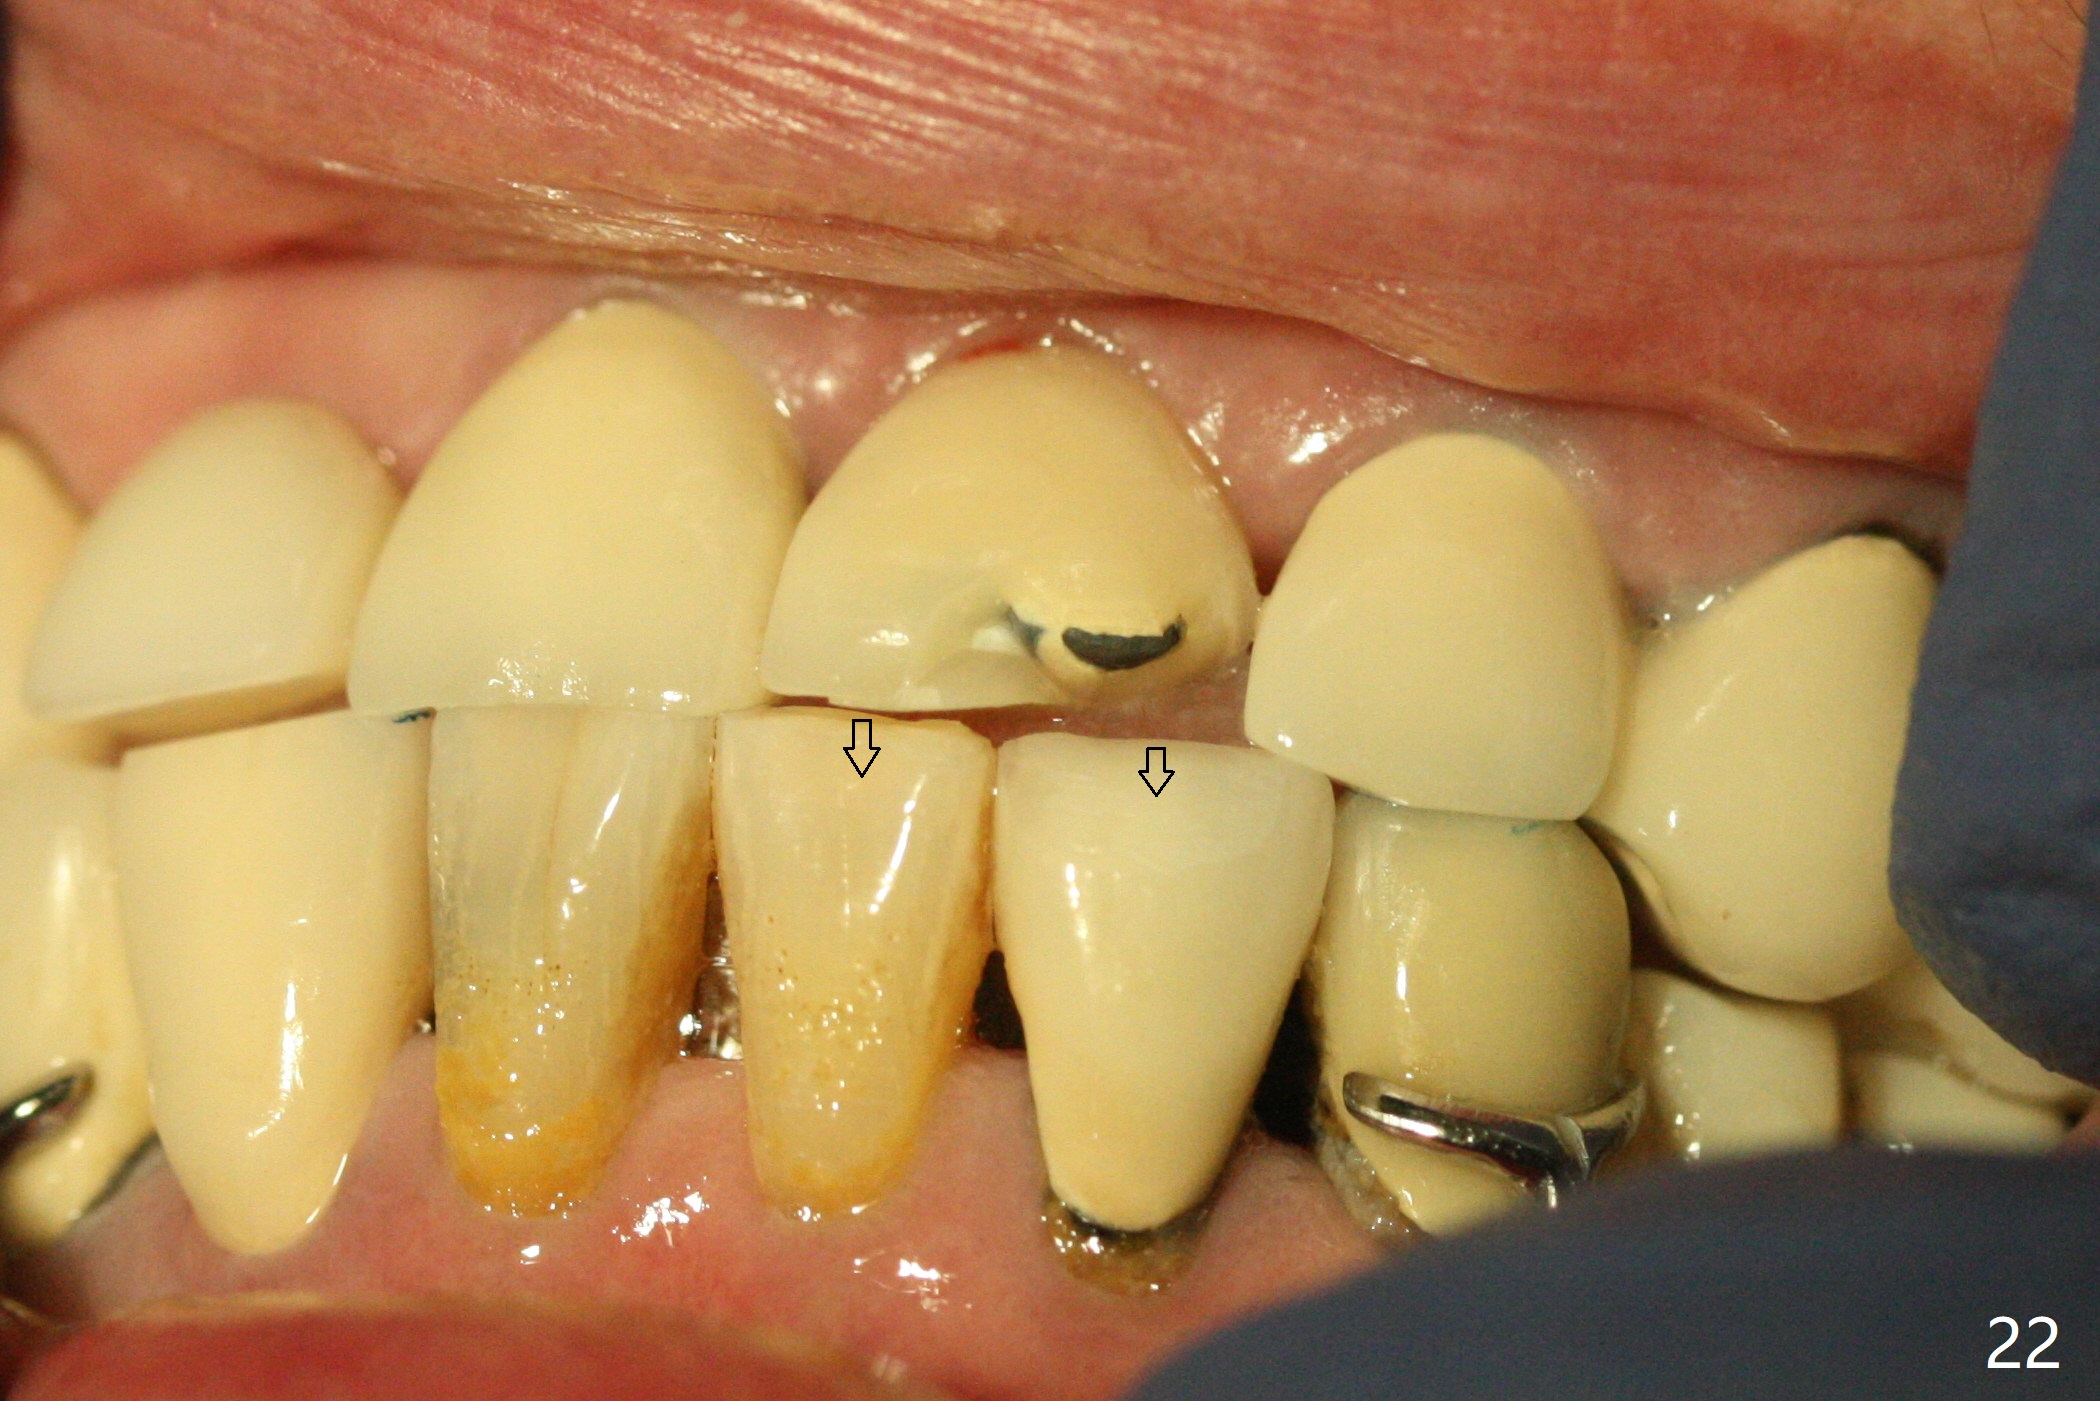

The buccal contour at #9 seems to be slightly concave preop (Fig.1,2 (*)). In fact the buccal plate is found to be lost when the tooth is extracted. Osteotomy is initiated as palatal as possible apical, but the occlusion dictates the coronal end of the osteotomy should be buccal, leaving the buccal gap ~ 2 mm for bone graft. The initial osteotomy (18 mm deep) appears to be close to the Incisive Foramen (Fig.3 blue dashed line). The nasal floor appears to be intact when the drill is removed. Subsequent osteotomy is adjusted so that the apical end of the osteotomy moves distal; when a 3.8x15 mm dummy implant is partially placed, there is clearance (Fig.4). It remains so when a definitive implant is seated (Fig.5); Vanilla graft is placed (Fig.5 *) before placement of a 4.5x5.5(3) mm abutment. More allograft is placed when an immediate provisional is fabricated (Fig.6 arrow and *). The gingiva remains to be recessive 1 month postop (Fig.7). It seems to be related to the bulky gingival margin of the provisional (Fig.8 *). After trimming the latter (Fig.9 *), the gingival margin immediately returns close to normal (Fig.10). The gingival margin is even between #8 and 9 two months postop, but the bone graft is exposed apically (Fig.11 ^). It may heals by itself. Otherwise debridement, regraft, PRF and suture are pending. The coronal portion of the socket heals 4 months postop (Fig.12). The gingival cuff forms by the immediate provisional (which is removed for impression) 4 months postop (Fig.13 *). While the full Zirconia crown at #7 remains intact (Fig.14), the PFM at #9 has porcelain chip (Fig.15). It is partially due to the occlusion; while the crown at #7 has clearance with the opposing dentition (Fig.16 *), the one at #9 has no. The access hole at #9 (Fig.17 *) seems to weaken the crown structure. There is no access hole at #7. No solid posterior support is another contributing factor for chip (Fig.18). The buccal plate has mild atrophy at #7 and 9 (Fig.19 *). A piece of bone graft is being expelled apically at #9 (Fig.20 >) and is removed subsequently (Fig.21). Before impression for repacking porcelain, the opposing incisal edge has been shortened (Fig.22 arrows, as compared to Fig.16). Since the ideal access hole is at the incisal edge (Fig.25 black circle), buccal to the existing one (Fig.24 A), the abutment is torqued before the repaired crown is recemented (Fig.23). Finally the crown has occlusal clearance (Fig.26). Porcelain chips again around the access hole of PFM 1.5 years post 2nd cementation. The dense bone at the crest (*) cannot explain why the abutment is not loose, since it remains incompletely seated (>). As it was trimmed short, an angled abutment is used (Fig.28). The coronal end is lingual, while #9/24 is edge to edge. The lingual aspect of the coronal end of the abutment is heavily trimmed to reduce bulkiness. To prevent chip, Zirconium crown will be fabricated in spite of the fact that it does not match the PFM of #8 (potential shade discrepancy). The patient is pleased with the new Zirconia crown (Fig.29).